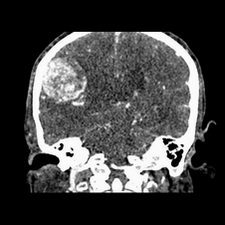

标题: CT25808:男,48岁,头痛多年,近段时间头痛加重伴步态不稳 [打印本页]

标题: CT25808:男,48岁,头痛多年,近段时间头痛加重伴步态不稳

平扫:右颞顶叶病灶呈等低密度伴大面积水肿,脑室受压变形。增强:病灶显著强化。考虑淋巴瘤或黑色素瘤。

1)不排除黑色素瘤可能;建议行mri检查。2)大脑镰下疝。3)脑积水(梗阻性)。